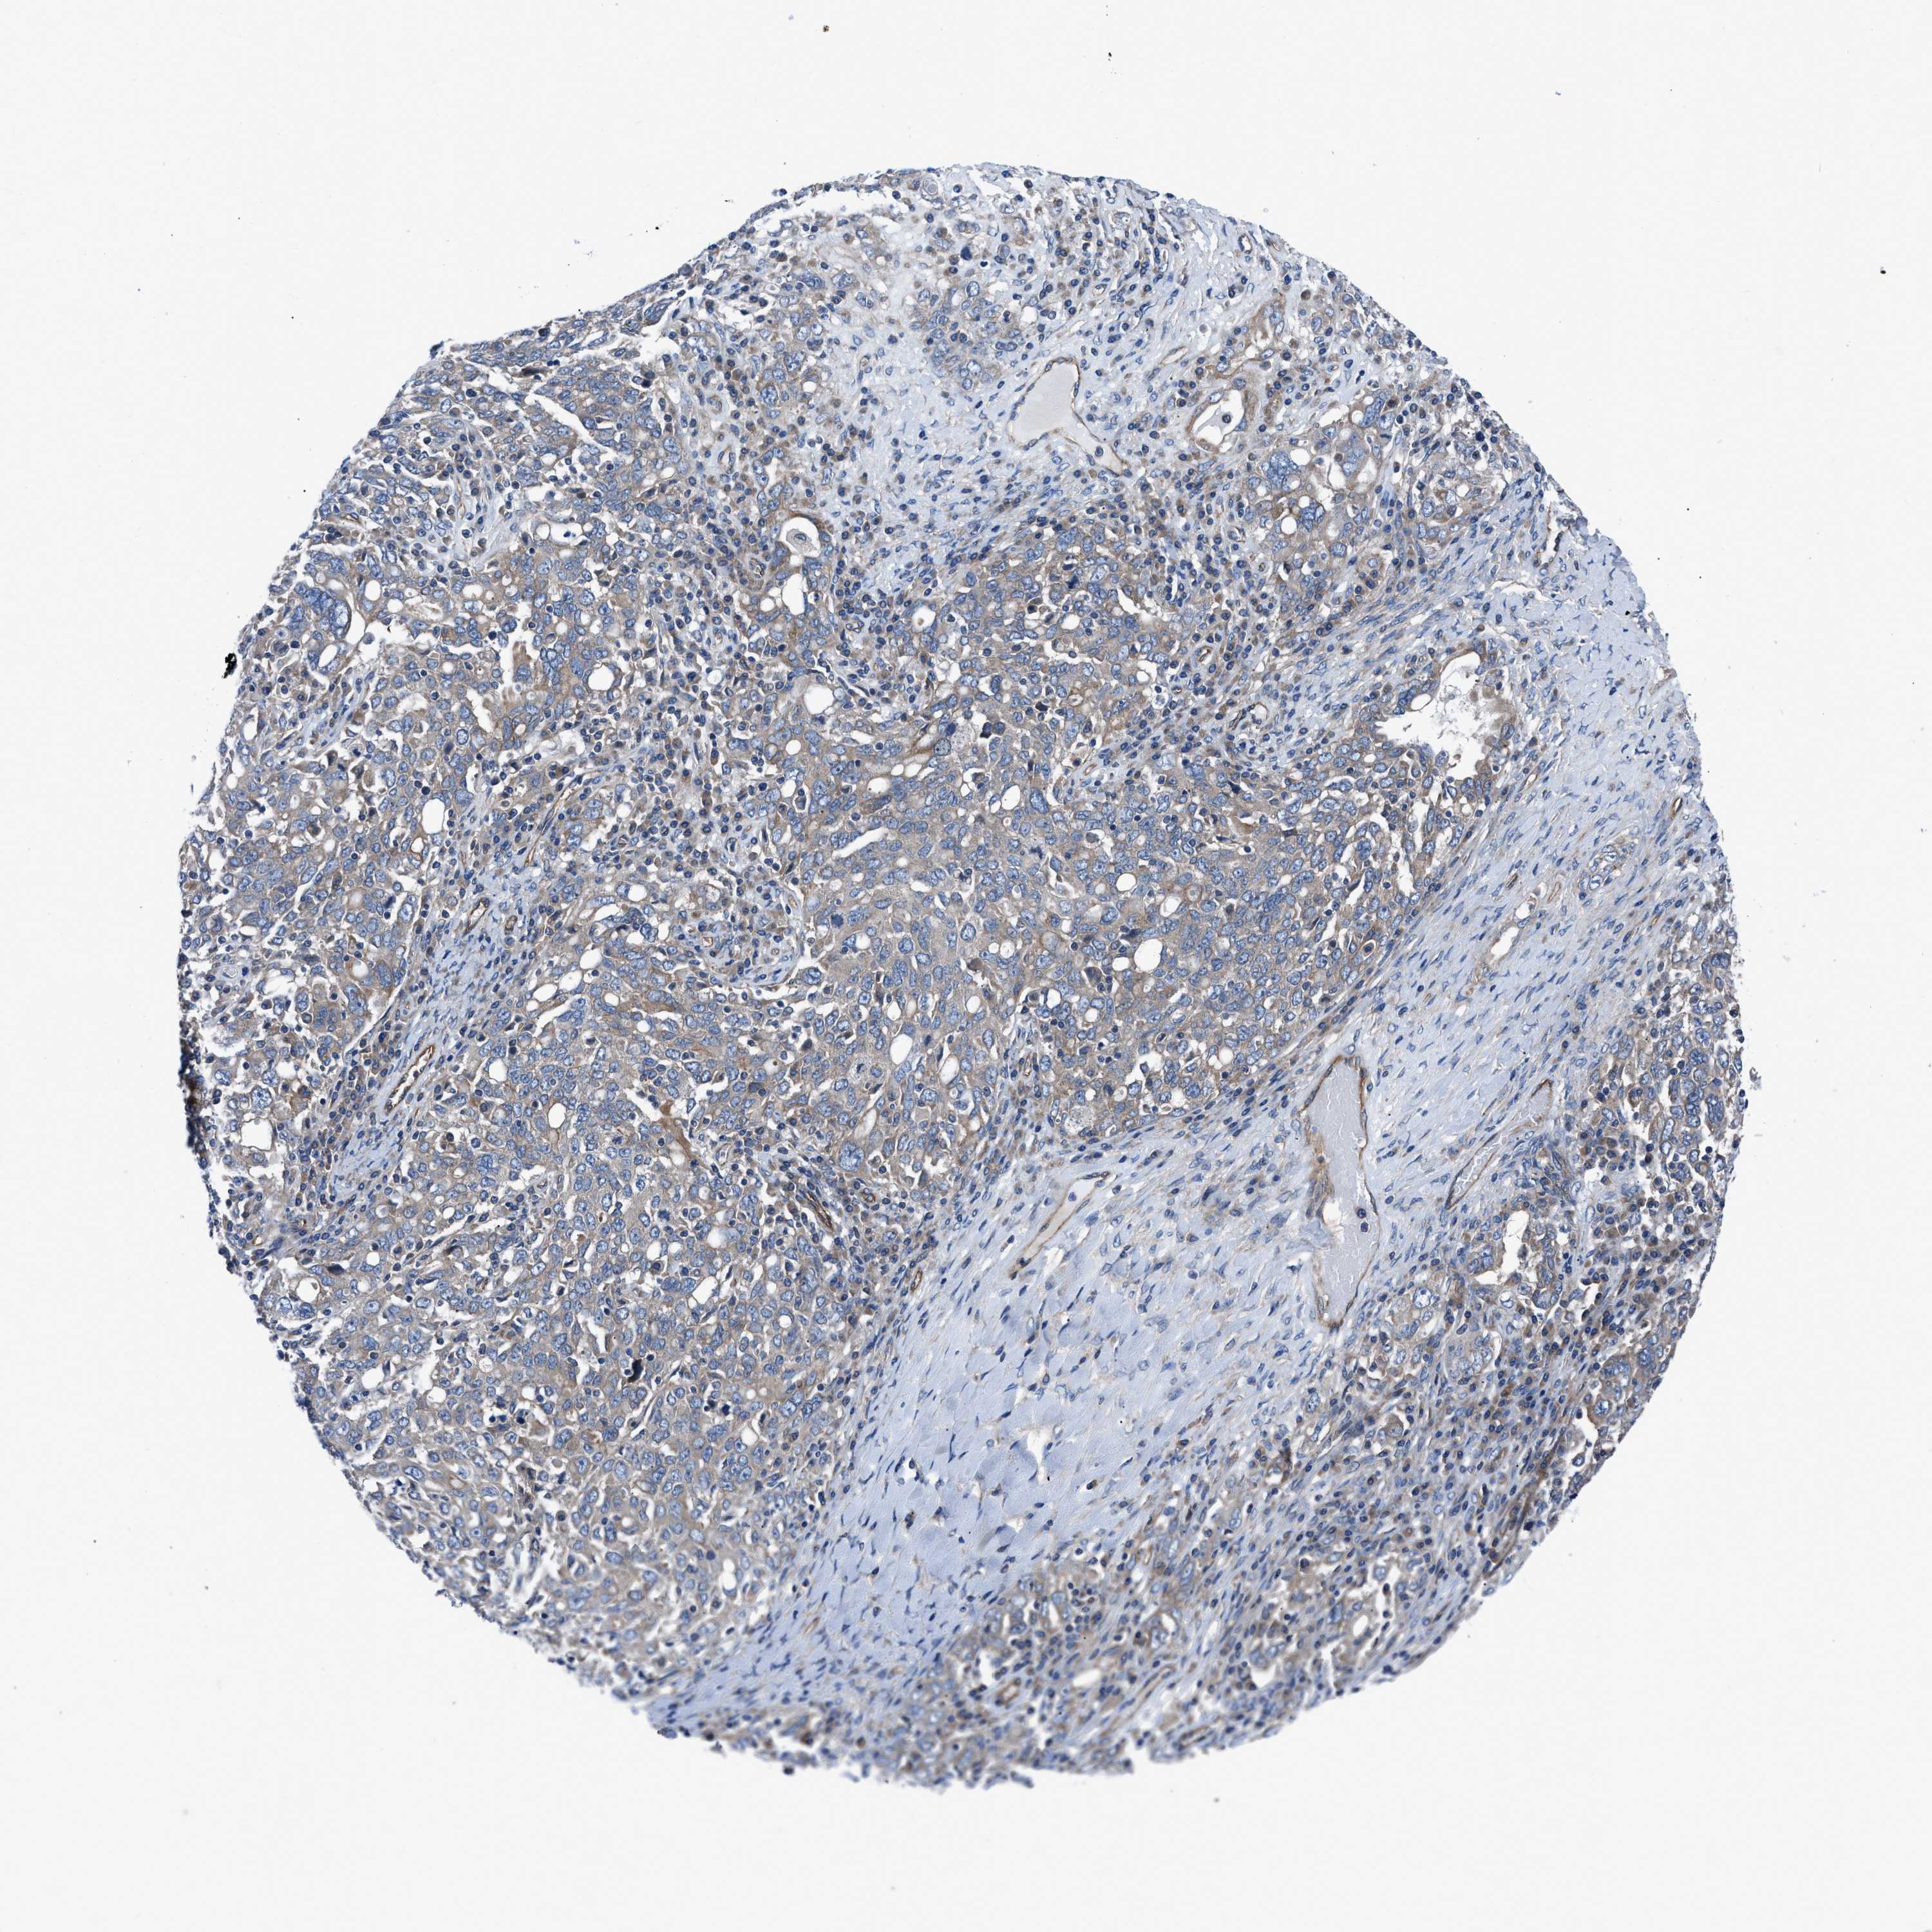

OVARIAN CANCER - Protein expressioni

A mouse-over function shows sample information and annotation data. Click on an image to view it in a full screen mode. Samples can be filtered based on level of antibody staining by selecting one or several of the following categories: high, medium, low and not detected. The assay and annotation is described here.

Note that samples used for immunohistochemistry by the Human Protein Atlas do not correspond to samples in the TCGA dataset.

Antibody stainingi

Antibody staining in the annotated cell types in the current human tissue is reported as not detected, low, medium, or high, based on conventional immunohistochemistry profiling in selected tissues. This score is based on the combination of the staining intensity and fraction of stained cells.

Each image is clickable and will lead to virtual microscopy that enables deeper exploration of all samples and also displays staining intensity scores, fraction scores and subcellular localization as well as patient and tissue information for each sample.

Antibody HPA016605

Staining

High

Medium

Low

Not detected

Intensity

Strong

Moderate

Weak

Negative

Quantity

>75%

75%-25%

<25%

None

Location

Nuclear

Cytoplasmic/membranous

Cytoplasmic/membranous,nuclear

Cystadenocarcinoma, serous, NOS

Carcinoma, endometroid

Cystadenocarcinoma, mucinous, NOS

Carcinoma, NOS